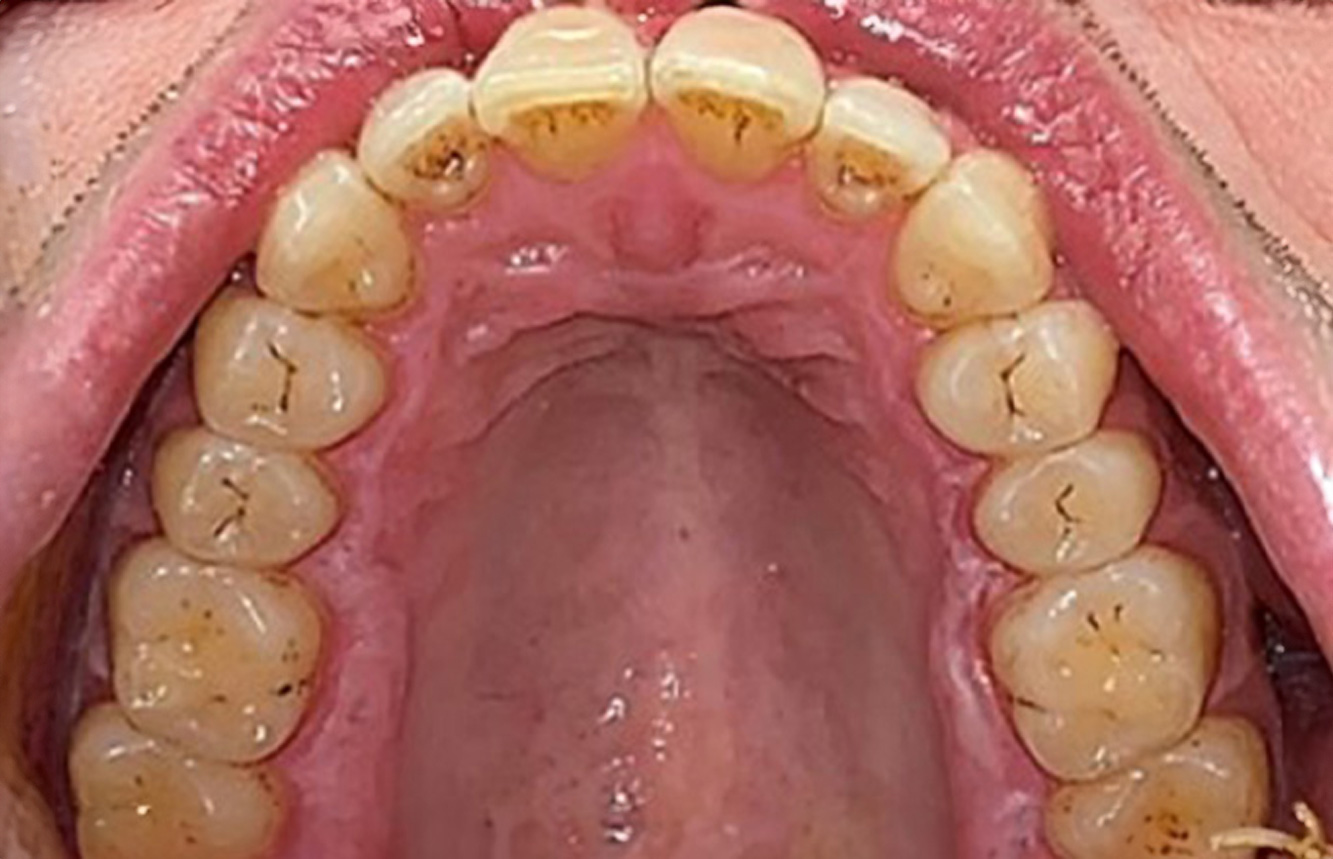

La paziente sana con precedente patologia parodontale

Questa paziente di 68 anni non presenta alcuna patologia precedente né segue alcuna terapia che possano ritenersi rilevanti dal punto di vista odontoiatrico, e il suo stile di vita non comporta alcun rischio particolare. La paziente ha due impianti (3° quadrante, da cinque anni) e una precedente patologia parodontale (parodontite allo stadio IV, grado B) con perdita del dente. Al momento le condizioni parodontali sono stabili, tuttavia la parodontite aumenta in misura significativa le complicazioni biologiche degli impianti e c'è dunque il rischio di perdita dell'impianto (21). Per la seduta di profilassi si possono formulare quattro consigli. di più